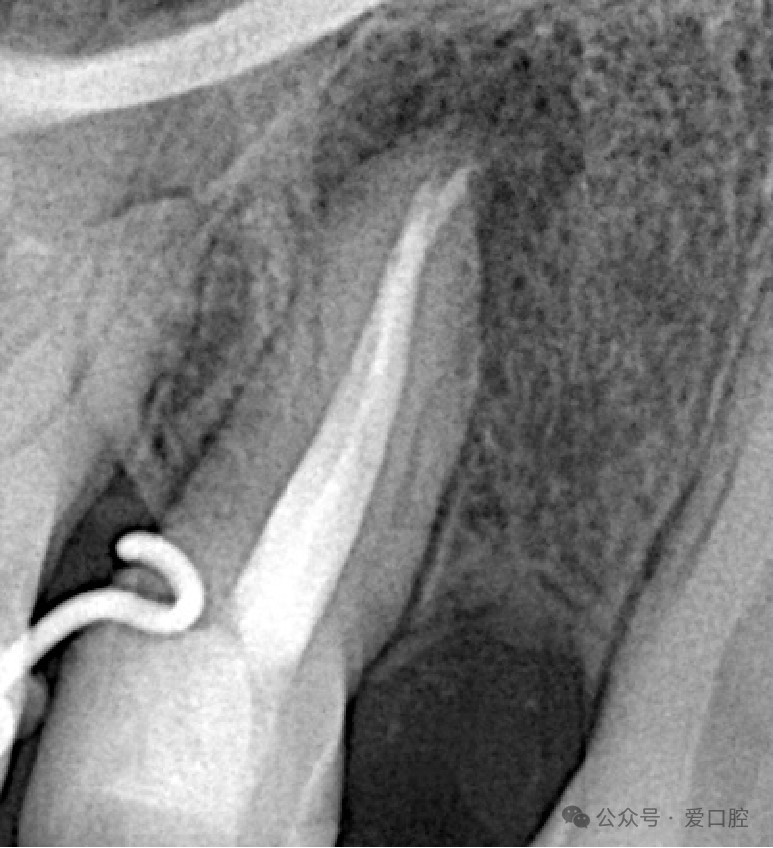

处置:15安放橡皮障后,去暂封,疏通,3%次氯酸钠溶液冲洗,Eddy荡洗(20秒3次), 蒸馏水冲洗,17%EDTA溶液冲洗,蒸馏水置换,吸干,AHplus糊剂+牙胶尖,热牙胶垂直加压法充填,流体封闭根管口,冠方树脂充填,调合,抛光。

医嘱:勿咬硬物,定期复查。